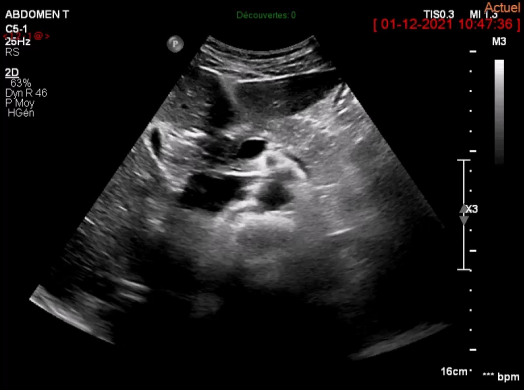

Echographie chez les candidats à la donation du lobe gauche du foie